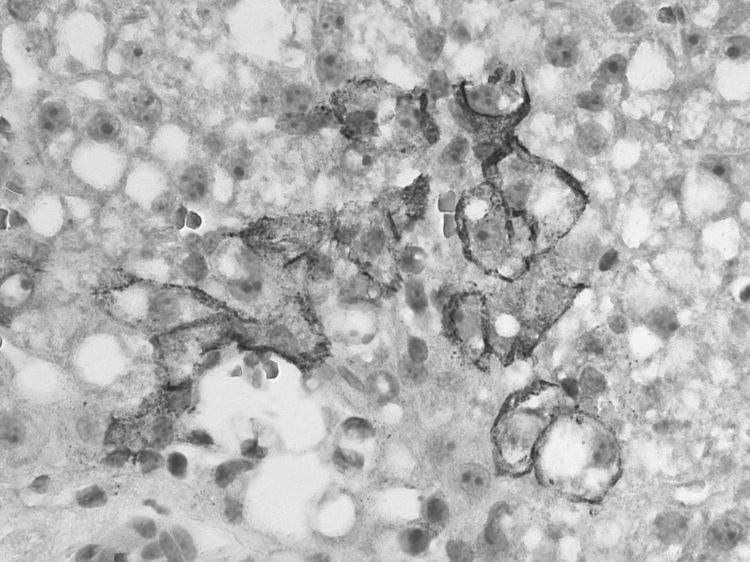

Three clusters of organ transplant-associated lymphocytic choriomeningitis virus (LCMV) transmissions have been identified in the United States; 9 of 10 recipients died. In February 2011, we identified a fourth cluster of organ transplant-associated LCMV infections. Diabetic ketoacidosis developed in the organ donor in December 2010; she died with generalized brain edema after a short hospitalization. Both kidneys, liver, and lung were transplanted to 4 recipients; in all 4, severe posttransplant illness developed; 2 recipients died. Through multiple diagnostic methods, we identified LCMV infection in all persons, including in at least 1 sample from the donor and 4 recipients by reverse transcription PCR, and sequences of a 396-bp fragment of the large segment of the virus from all 5 persons were identical. In this cluster, all recipients developed severe illness, but 2 survived. LCMV infection should be considered as a possible cause of severe posttransplant illness.

美国已发现 3 起与器官移植相关的淋巴细胞性脉络丛脑膜炎病毒 (LCMV) 传播集群;10 名受者中有 9 名死亡。2011 年 2 月,我们发现了第 4 起与器官移植相关的 LCMV 感染集群。器官供者于 2010 年 12 月发生糖尿病酮症酸中毒;她在短时间住院后死于广泛脑水肿。2 个肾脏、1 个肝脏和 1 个肺被移植给 4 名受者;4 人均出现严重的移植后疾病;2 名受者死亡。通过多种诊断方法,我们在所有受者中均发现了 LCMV 感染,包括供者和 4 名受者的至少 1 份样本通过逆转录 PCR 检测到,以及 5 人均来自病毒大节段的 396 个碱基片段的序列完全相同。在该集群中,所有受者均出现严重疾病,但有 2 名存活。应考虑 LCMV 感染为严重移植后疾病的可能病因。